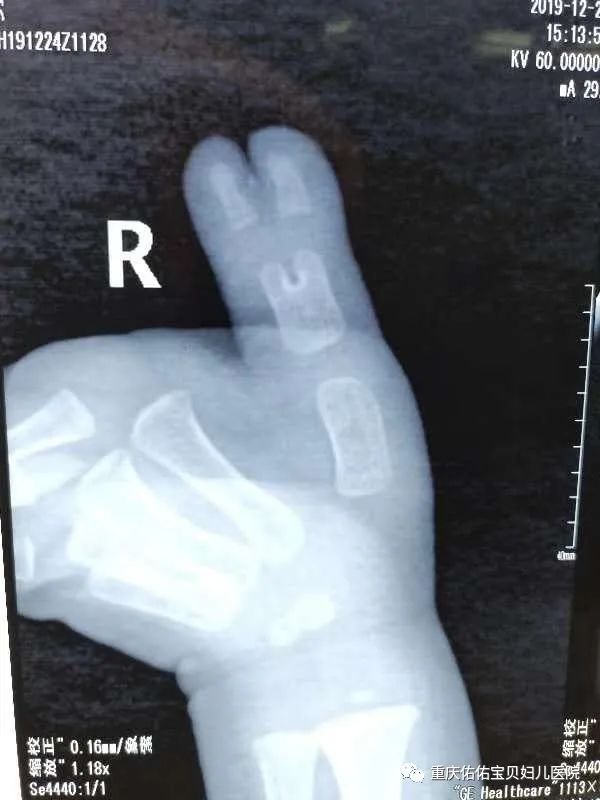

乐乐(化名),今年快2岁了,出生时发现孩子右手拇指多指畸形,随着年龄增长,多指逐渐增大,并影响正常拇指的活动。

(术前拍片)

在多指患儿中,乐乐算是比较晚进行治疗的,拇指骨骼已经发育明显,对手术的要求也更高。看到孩子的情况后,南教授立即跟家长沟通为孩子制定了诊疗方案、安排手术。